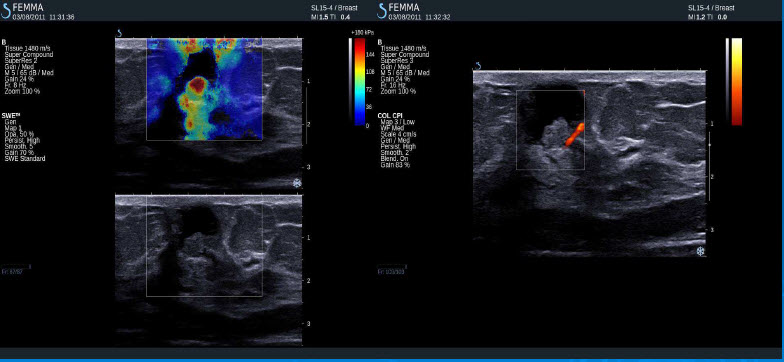

Pozitivní výsledky elastografie / histologicky potvrzená malignita

Invazivní duktální adenokarcinom